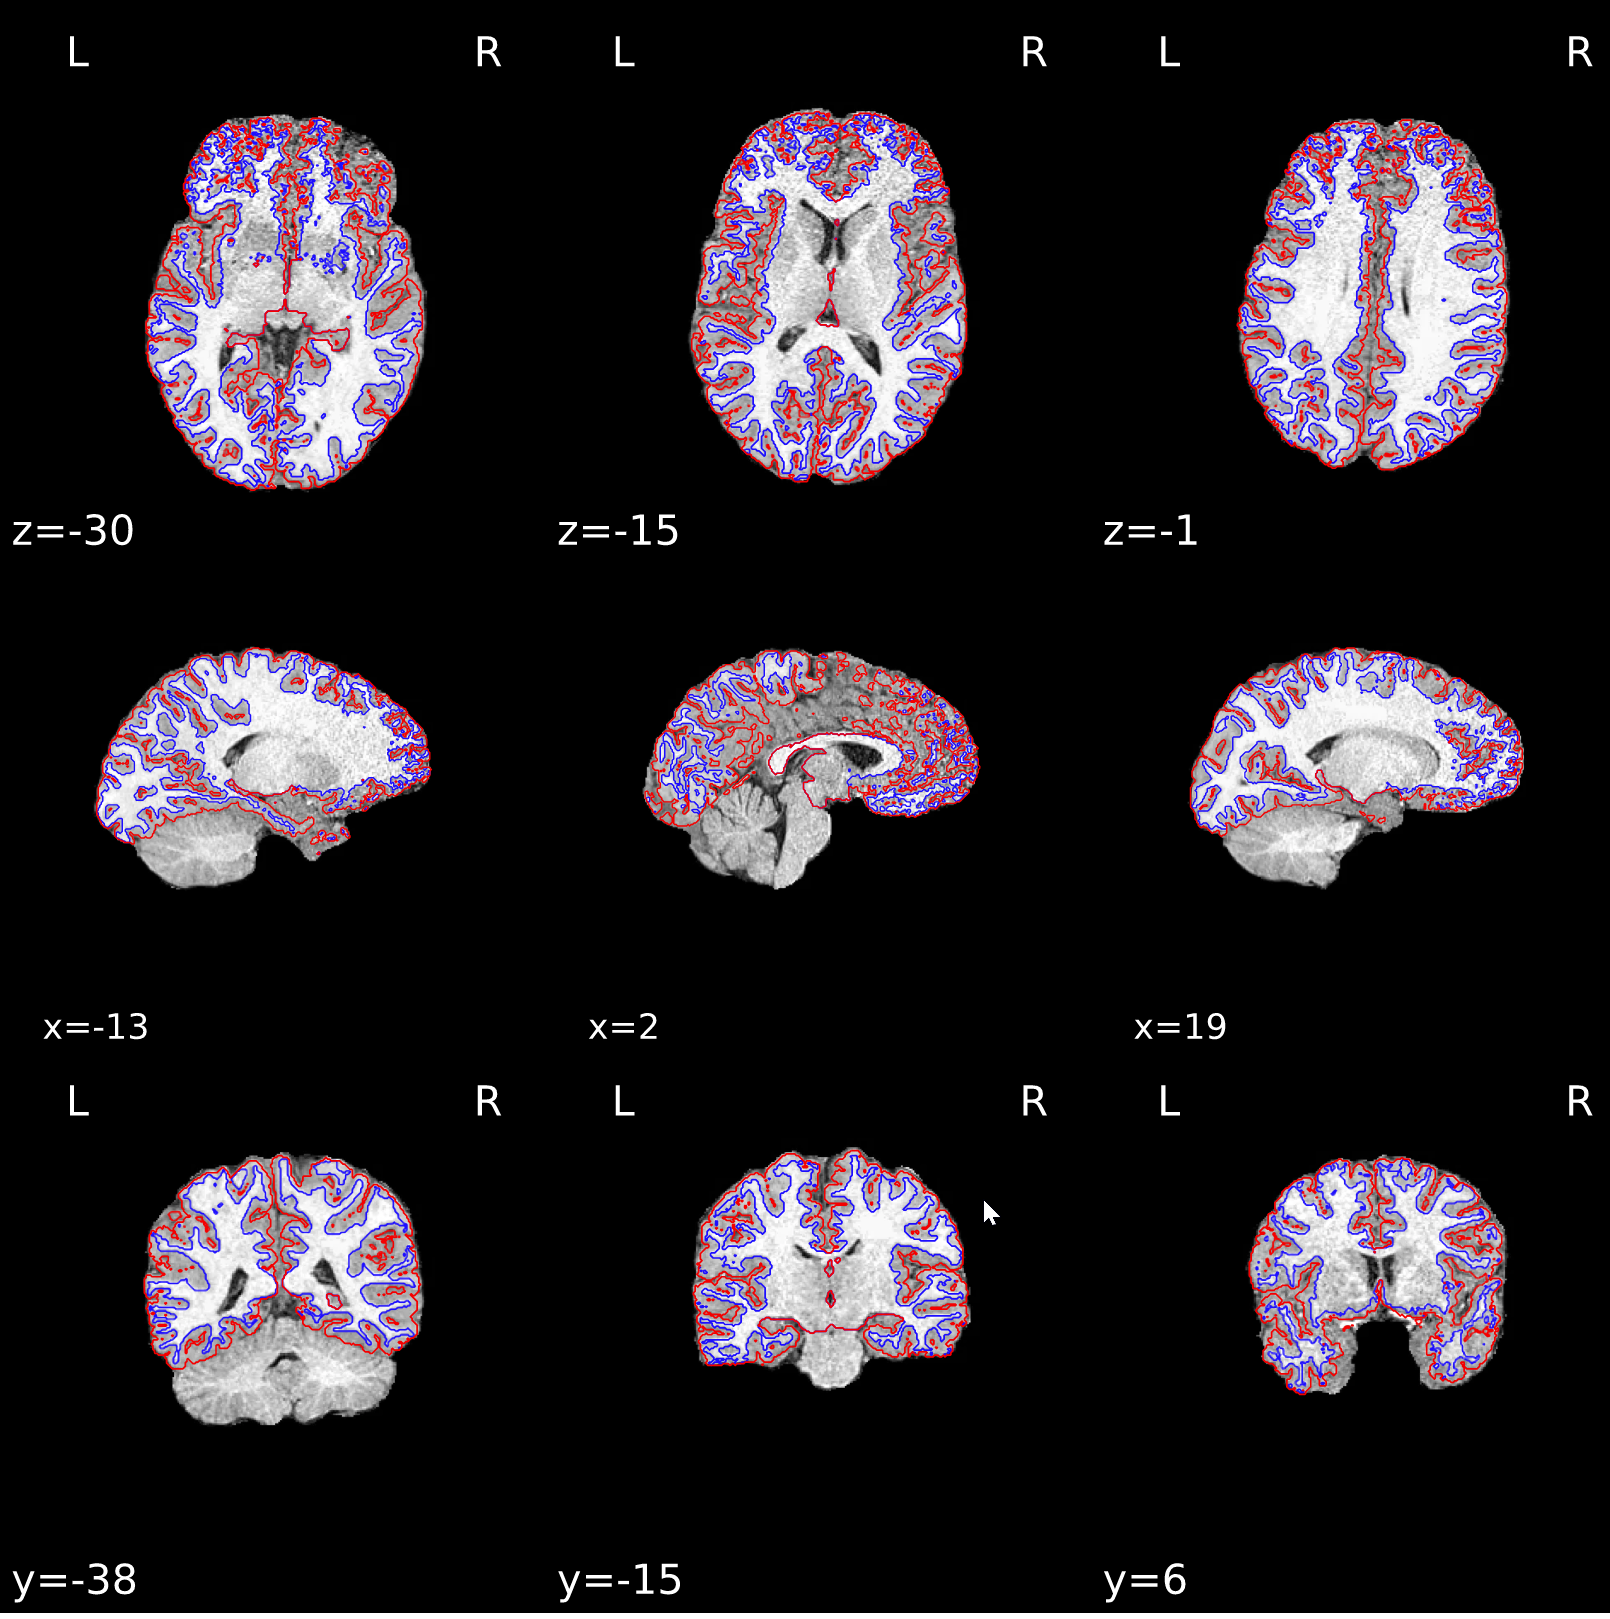

Last case had a negative influence on surface reconstruction